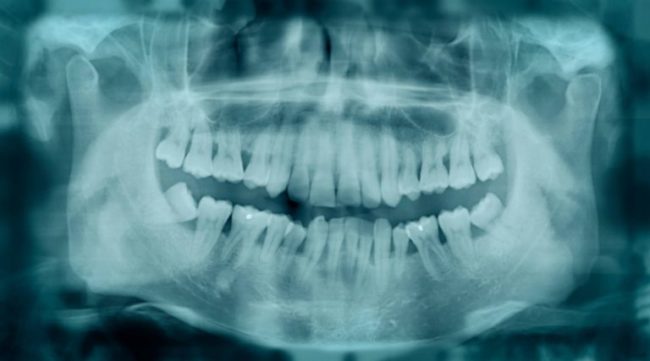

Cada vez mais pessoas sofrem com problemas de dentes tortos, os que os diferenciam são os tipos de desalinhamento dentário que em alguns casos podem ser mais discretos, em outros mais expressivos. Além de prejudicar a funcionalidade e a estética bucal, dentes tortos podem ser causados por diversos motivos e é sobre esse assunto que…